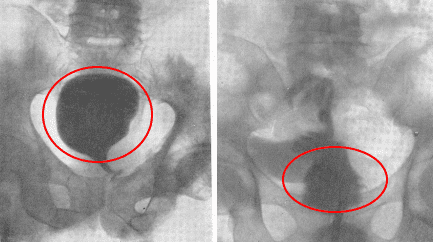

أستطيع أن أرى الرجال الذين يزورونني بسبب التهاب البروستاتا أو تضخم البروستاتا الحميد كل يوم. في الواقع، هذه الأمراض هي حالات ما قبل سرطانية غدة البروستاتا.

كما ترى، ترتبط هذه المشكلات ارتباطًا مباشرًا بممارسة الجنس بانتظام. عندما يتوقف الرجل عن ممارسة الجنس بانتظام، تصاب غدة البروستاتا بالاحتقان، ونتيجة لذلك، يتسبب ذلك في حدوث التهاب ويوقف إنتاج الهرمونات المهمة. بدون علاج طويل الأمد، يتطور التهاب البروستاتا إلى تضخم البروستاتا الحميد الذي يتحول بعد ذلك إلى سرطان.

سرطان البروستاتا ناتج عن عدم ممارسة الجنس لفترة طويلة. توفي رجل 60 سنة.